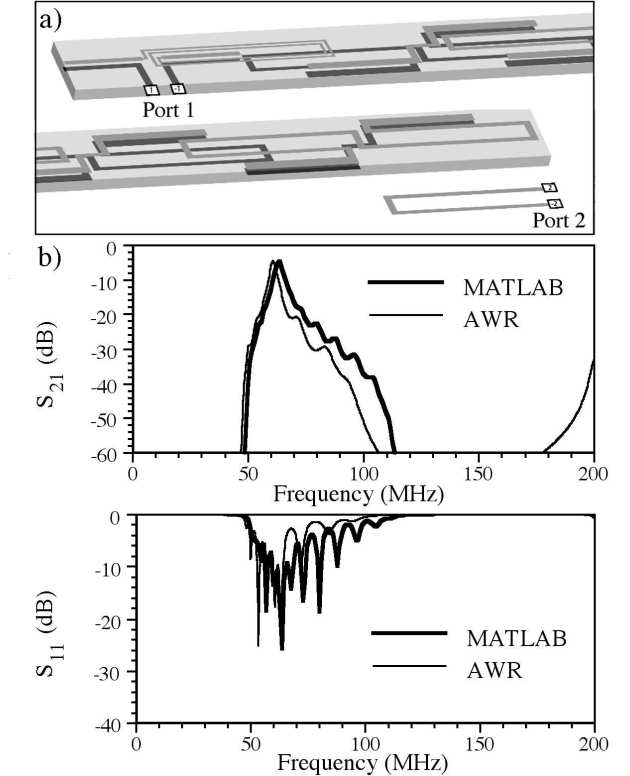

Khoonsake Segkhoonthod, Richard Syms and Ian R. Young

We have modeled a catheter-based RF receiver for internal magnetic resonance imaging. The device consists of a double-sided thin-film circuit, mounted on a hollow catheter. The system was originally designed for biliary ductal imaging, but is also potentially useful for vascular imaging. Signals are detected using a resonant L-C circuit at the catheter tip, transmitted along the catheter using an array of coupled L-C resonators, and coupled into a conventional RF system using a demountable inductive transducer. Protection against external B1 and E fields is obtained by using figure-of-eight-shaped elements with an electrical length shorter than that of an immersed half-wave dipole. Electromagnetic modeling software (AWR Microwave Office) has been used to analyze a system designed for 1H imaging at 1.5 T, determine the effect of the tissue surround, demonstrate signal detection and transmission and verify intrinsic safety.

| Detector simulation: a) AWR model; b) frequency variations of S11 and S21 as predicted by AWR and MATLAB. |